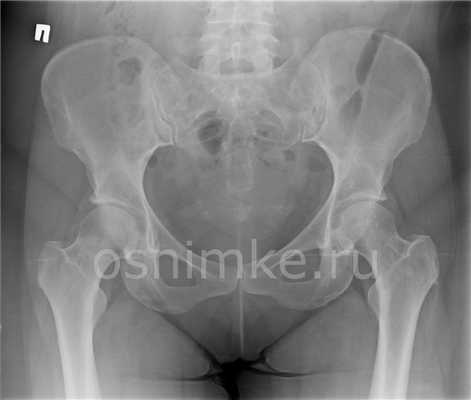

Рентген костей таза и тазобедренных суставов может проводиться в трех проекциях: переднезадней (ПЗ), заднепередней (ЗП) и латеральной (боковой). На снимке спереди видны тазовые кости от верхней части гребня подвздошной кости до проксимального отдела диафиза бедренной кости, лобковая и седалищная кости, тазобедренный сустав, запирательные отверстия, большие вертелы проксимального отдела бедра в профиль.

На снимке сбоку визуализируется крестец, копчик, пояснично-крестцовый переход, наложенные друг на друга бедренные кости и верхняя часть бедра.

Что показывает рентген таза?

Визуализируя гребень подвздошной кости, крестец, подвздошно-крестцовые сочленения, большое тазовое кольцо, лобковую и седалищную кости, проксимальный отдел бедра, рентген таза может показать: анатомические нарушение формы таза или тазобедренного сустава; переломы таза; перелом, вывих или артрит тазобедренного сустава; опухоли костей таза (остеосаркомы).